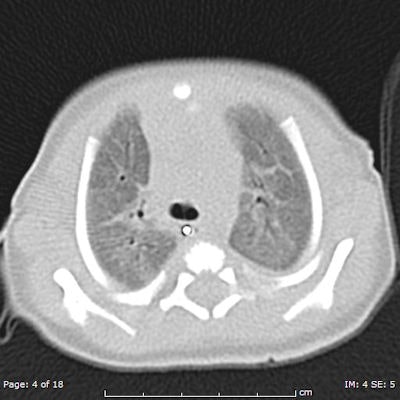

![Chest CT of 8-day-old girl with respiratory distress (80 kV, 51 average effective mAs, CTDIvol = 2.3 mGy, DLP [dose length product] = 33 mGy cm, E[effective dose] = 1.1 mSv. CT was performed to exclude congenital lung abnormalities because of family history and small volume lungs. Image shows ground glass opacity and septal lines consistent with respiratory distress syndrome. In all four figures, CTDIvol and DLP are expressed in terms of the 16 cm CT dosimetry phantom; these should be divided by approximately two to be expressed in terms of the 32 cm CT dosimetry phantom. Effective dose was calculated from DLP using conversion coefficients specific to this scanner and using the International Commission on Radiological Protection Publication 103 definition of effective dose. All images courtesy of Zoe Brady, PhD.](https://img.auntminnieeurope.com/files/base/smg/all/image/2012/08/ame.2012_08_15_08_57_30_715_2012_08_15_pediatrict_CT_pic1.png?auto=format%2Ccompress&fit=max&q=70&w=400)

The researchers compared average dose values at the Royal Children's Hospital (RCH) in Melbourne with international DRLs for common pediatric CT examinations. They found the use of 80 kV for both chest and abdomen/pelvis imaging in children younger than 5 years old leads to a significant dose saving, but conceded there is potential for dose optimization by reducing scan lengths for body examinations for children older than 5 years old. The plan now is to review these protocols to determine whether there is appropriate justification for the extended scan lengths.

Furthermore, the reference mAs values for chest imaging must be justified, particularly relative to the abdomen/pelvis examination values for the same age groups, according to Brady. Because of the inherent contrast in the chest and lack of attenuating tissue, it was expected that these values might be lower for chest examinations than for abdomen/pelvis examinations, but in fact in the older age group they were found to be higher.

The LDRLs across all age categories were 18-45 mGy (CTDIvol) and 250-700 mGy cm (DLP) for brain examinations; 3-23 mGy (CTDIvol) and 100-800 mGy cm (DLP) for chest examinations; and 4-15 mGy (CTDIvol) and 150-750 mGy cm (DLP) for abdomen/pelvis examinations. Effective dose estimates were 1.0-1.6 mSv, 1.8-13.0 mSv and 2.5-10.0 mSv for brain, chest, and abdomen/pelvis examinations, respectively. The RCH mean CTDIvol and DLP values were similar to or lower than international DRLs.